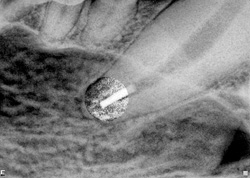

The SimpliFill obturation plug is in place and the twist away removable carrier has already been removed. (Photo courtesy of Dr. D.H. DeForge)